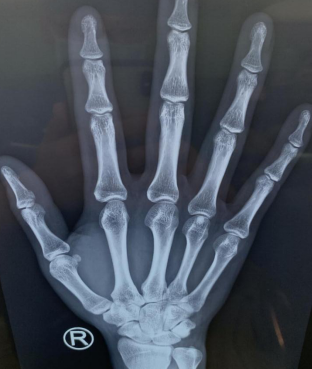

兩天后,劉某感覺右手拇指疼痛加重、活動受限,于是來到徐州仁慈醫(yī)院。手外科四病區(qū)收治后,拍片檢查看不出來魚刺具體位置,只能根據(jù)劉某的描述,拆除右手傷口縫線,延長傷口,在大概2厘米的位置終于找到了魚刺,原來魚刺藏在了橈腕關(guān)節(jié)囊內(nèi)。

術(shù)前CT